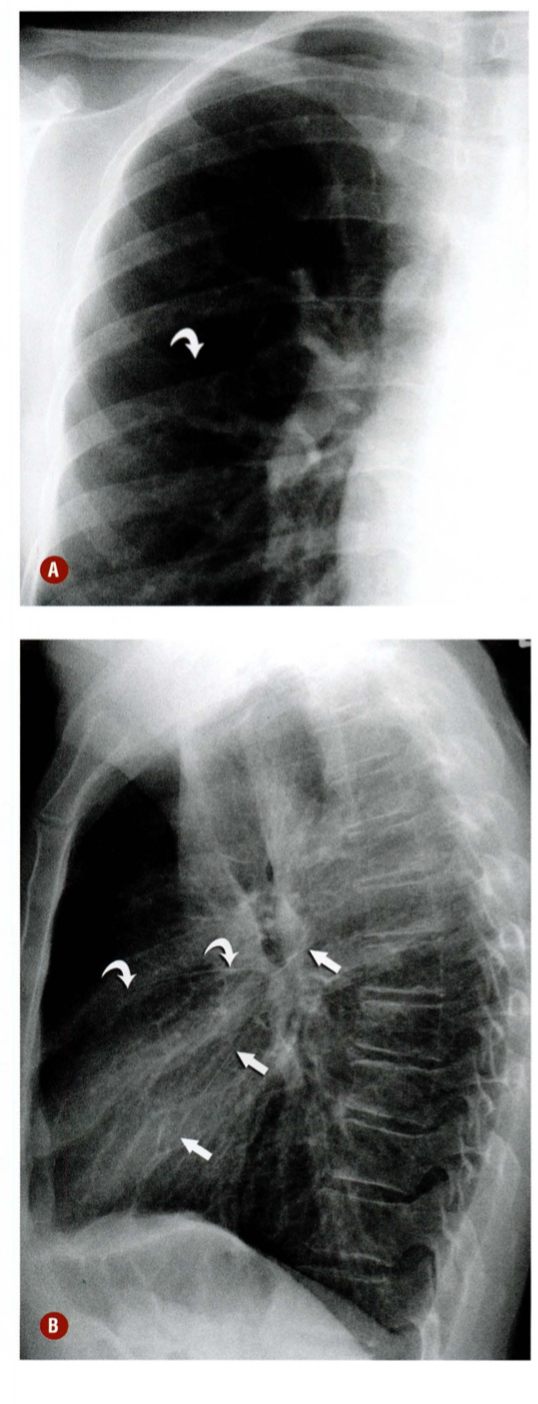

Descreva as fissuras apontadas pelas setas e os lobos pulmonares

Qual a alteração demonstrada pelas setas?

Qual estrutura apontada?